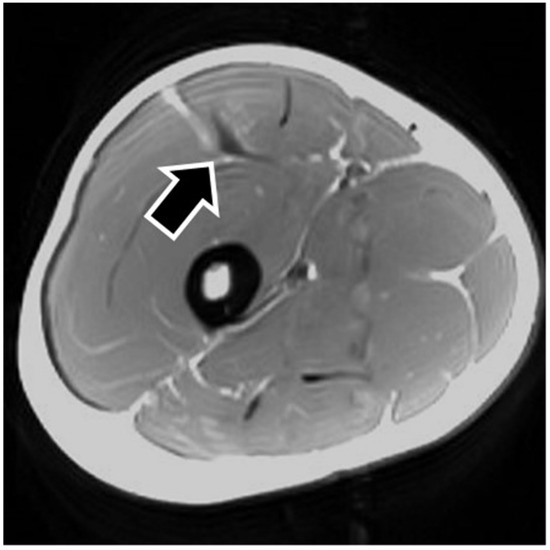

MRI findings are shown in Table 1. In eight of the RF strain injuries, a low signal area was noted in the central tendon (Figure 2). In four of the RF strain injuries, a low signal area was noted in the myofascial junction of the RF (Figure 3). In four of the RF strain injuries, the axial T1-weighted image did not show a low signal (Figure 4). The longitudinal range of the injured region in the 12 RF that showed a low signal area in MRI was approximately 8.8 cm (range, 4–17 cm). When the injured part was limited to the central tendon, the longitudinal range of the injured region was approximately 10.5 cm (range, 5–17 cm).

The MRI of a grade 1 strain is of a feathery appearance. Hemorrhage and fluid around the central tendon greatly suggest an acute grade 2 strain. In chronic or healing RF strains, there may be a fibrous encasement of the central tendon, characterized on MRI as T1 and T2 linear low signal around or adjacent to the central tendon [7]. The MRI showed a low signal area in this study so that the central tendon injured RFs were speculated as grade 2.

Figure 4. Noninjured rectus femoris muscle. The figure shows an example of noninjured rectus femoris muscle. The axial T1-weighted image does not show a low signal in the central tendon (black arrow).